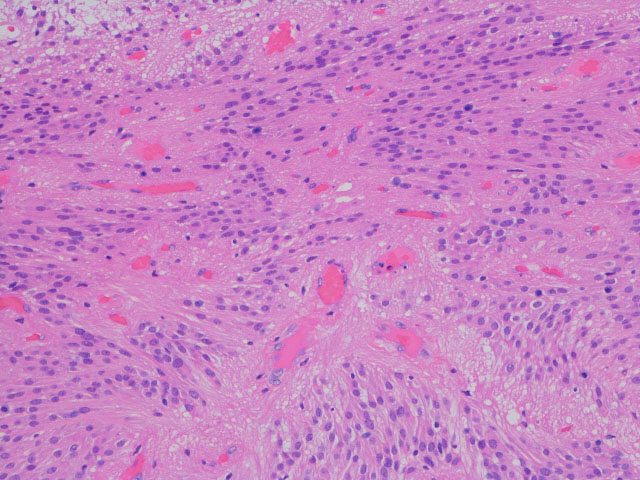

- 病理像では,好酸性の胞体 glassy eosinophilic cytoplasm を有する不整形の巨細胞の存在が特徴です

- 核は,多型で複数核 pleomorohic binucleate to multinucleate,クロマチンは粗,核小体が明瞭で神経節細胞様の大型のものもみられます

- 腫瘍細胞にはGFAP, vimentine, S-100が陽性で,巨細胞はNF, NSEなどが陽性となることがあります

- 血管増殖像はなく,核分裂もなく,組織の異型性に反して臨床的には良性腫瘍の性格を呈します

SEGAの病理像

基本的には,大きくて太った細胞 large plump cells で構成されます。gemistocytic astrocytesにています。

polygonal cells, ganglionic-like cells with a clear nucleoli, and plump large tumor cells resembling gemistocytic astrocytes

multinucleated giant cells

perivascular pseudorosettes, sweeping fascicles